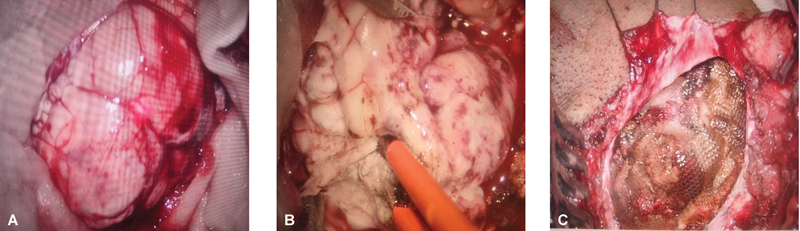

Lhermitte-Duclos disease (LDD) is a rare, autosomal dominant, dysplastic gangliocytoma of the cerebellum. It is a slow-growing benign tumor. The challenges in the surgical resection of these tumors lie in accurately delineating the tumor margin from the normal cerebellar parenchyma. Intraoperative ultrasound has the potential to overcome these limitations. A 30-year-old woman was diagnosed as having LDD showing a typical "tigroid" appearance on MRI. Intraoperative ultrasound was used to delineate the tumor margins and near-total resection was done via right suboccipital craniectomy. The diagnosis was confirmed on histopathological examination. Postoperatively there were no neurological deficits, and the patient is on regular follow-up for screening of Cowden's syndrome. We report this case to highlight the undervalued utility of intraoperative ultrasonography while dealing with patients with LDD. This modality serves as an effective tool to maximize the extent of resection without adding to postoperative morbidity.